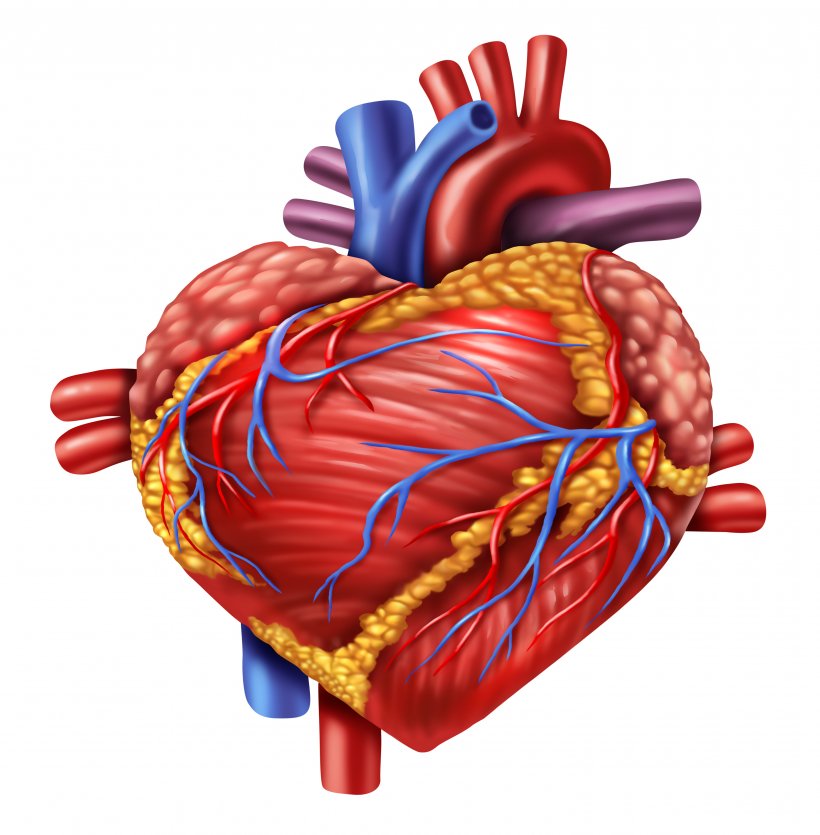

Анатомия здорового сердца: фотографии и иллюстрации